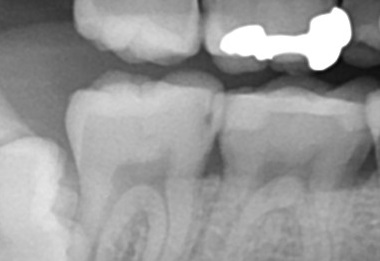

銀歯の虫歯の原因は?40代女性

• Before

After